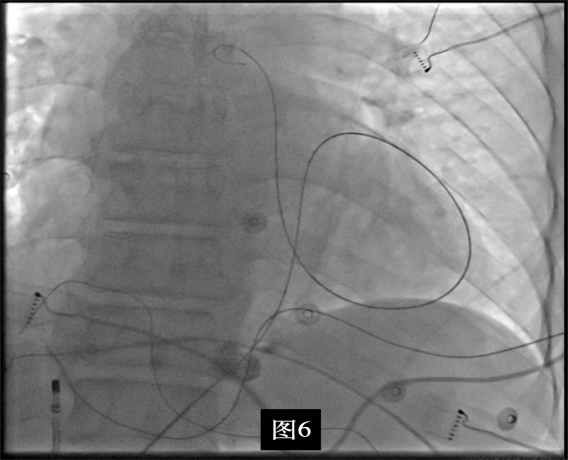

即穿刺股静脉,将消融大头送至冠状窦内,在GCV远端对应位置标测到最早点(图5绿色点)领先体表27ms,消融后早搏未能消失,周明礼评估起源点偏心外膜,能量依旧不能穿透损伤到起源点,内膜消融基本无效后,果断选择难度系数最为复杂的干性心包穿刺心外膜消融。在导丝的指引下,将消融大头送至心包层(图6),于外膜标测到靶点(图7黄色点)电位领先体表31ms,单极电位无r波且有顿挫,ssummit外膜离冠状动脉较近,比较危险,保证安全,进行了冠脉造影(图7),显示距离LAD和LCx有一定距离,相对安全,随即放电,2s室早消失,10s患者出现心率变慢,该区域走形迷走神经节,消融导致心率减慢,随后保证心率正常的情况下,消融够60s,随后观察半小时,早搏没有恢复,手术成功(图8)。经过不懈的努力,患者恢复了窦率,心脏功能也逐渐恢复正常,手术取得了圆满成功。